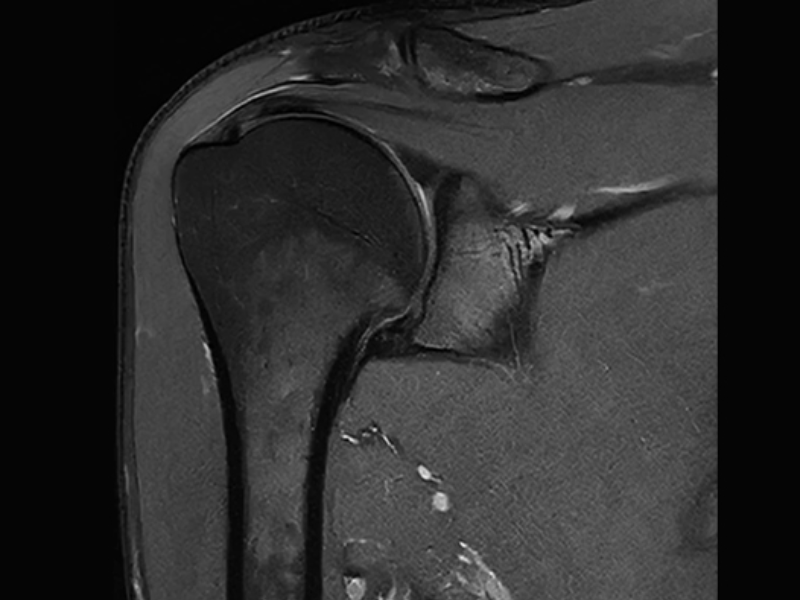

PD Shoulder with uAI DeepRecon

uAI DeepRecon

uAI DeepRecon provides an increase in both signal and resolution at the time of scanning or during post reconstruction using a convolutional neural network trained model.